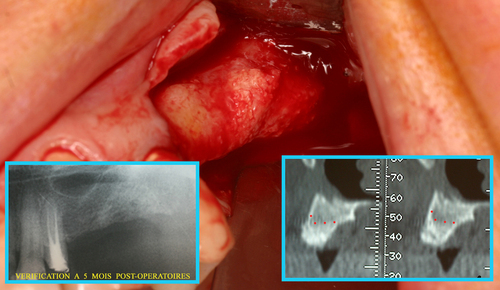

Les infections des dents provoquent  des lésions osseuses avec disparition du volume osseux au fur et à mesure que l’infection se propage dans l’os des maxillaires. (fig. 29)

Fig. 29

Les infections dentaires provoquent des pertes osseuses importantes

Cela interdit souvent le port d’une prothèse correcte ou la mise en place d’implants en remplacement des dents absentes.

Un rayonnement laser pénétrant utilisé sous eau oxygénée à 10 volumes permet de décontaminer tout l’os du maxillaire après l’extraction des dents (fig. 30)

Fig. 30

Décontamination du maxillaire après extractions

Cela permet d’envisager immédiatement une régénération osseuse qui est effectuée le jour même des extractions et le résultat à 5 mois postopératoires (fig.31) montre une régénération complète du massif osseux.

Fig. 31

Régénération osseuse du maxillaire